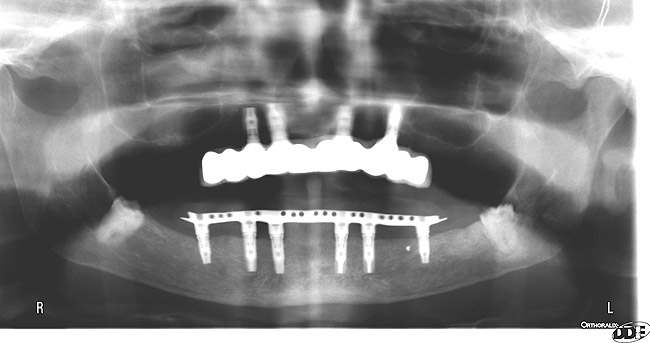

#4 Hybrid bridge framework case

This one isn’t that bad but not sure why the metal was included at all?? I’ve never seen anything like that and can only assume it is done to allow for a smaller more natural looking connector between the pontic and the abutment teeth. If that is the case then this is a rather ingenious plan. This may just be my ignorance of the bridge technique. I have been unable to locate anything supporting such a configuration.

These implants are placed far too distal. Ideal location is canine to lateral incisor. Premolar location creates a seesaw effect with the denture.